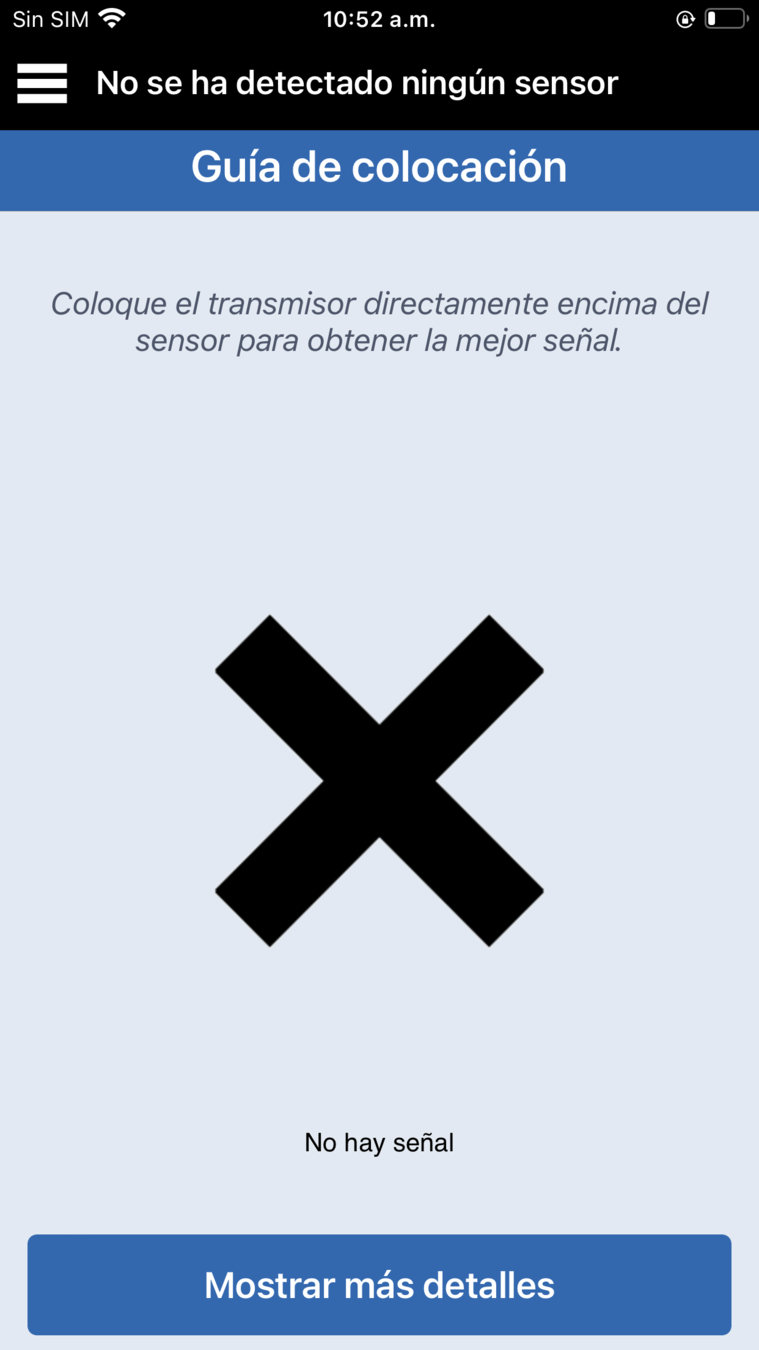

La barra de estado de la aplicación indicará Fase de calentamiento o No se ha detectado ningún sensor.

es posible que aparezca un mensaje emergente de alerta No se ha detectado ningún sensor. Solo tiene que tocar Ahora no.

A continuación, abra la guía de colocación en la aplicación yendo al menú principal >

Guía de colocación.

Verá una X negra al principio.

Levante con suavidad y mueva ligeramente el transmisor inteligente junto con el adhesivo para encontrar la ubicación con la señal más fuerte, algún punto entre las 2-3 barras o de buena a excelente.

Cuando mueva el transmisor, deje que pasen unos segundos para que se actualice la señal antes de volver a moverlo.

de dos o tres barras, deje el transmisor inteligente en esa posición sobre el brazo.

Cierre la guía de colocación tocando el icono del menú.